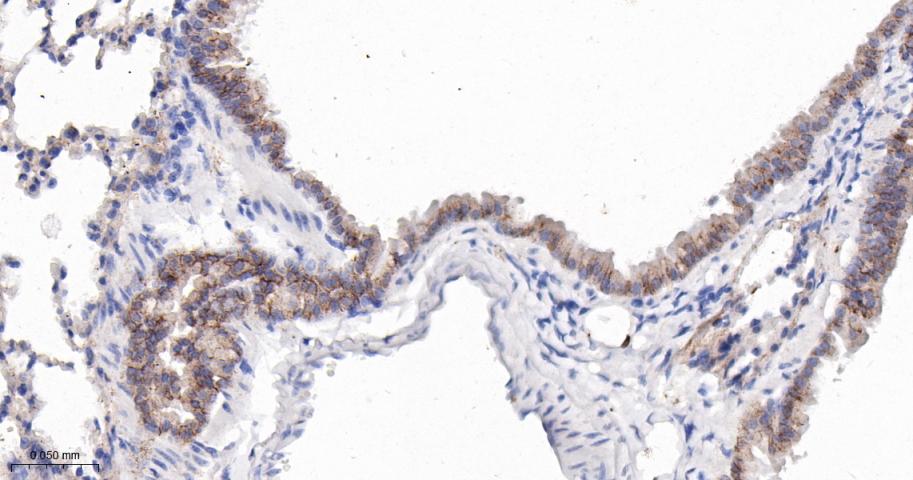

Paraformaldehyde-fixed, paraffin embedded Human Lung; Antigen retrieval by boiling in sodium citrate buffer (pH6.0) for 15 min; The section was incubated with CD166 Monoclonal Antibody, Unconjugated (bsm-61678R) at 1:200 overnight at 4°C, followed by conjugation to the bs-0295G-HRP and DAB (C-0010) staining.

Paraformaldehyde-fixed, paraffin embedded Rat Lung; Antigen retrieval by boiling in sodium citrate buffer (pH6.0) for 15 min; The section was incubated with CD166 Monoclonal Antibody, Unconjugated (bsm-61678R) at 1:200 overnight at 4°C, followed by conjugation to the bs-0295G-HRP and DAB (C-0010) staining.

Paraformaldehyde-fixed, paraffin embedded Mouse Lung; Antigen retrieval by boiling in sodium citrate buffer (pH6.0) for 15 min; The section was incubated with CD166 Monoclonal Antibody, Unconjugated (bsm-61678R) at 1:200 overnight at 4°C, followed by conjugation to the bs-0295G-HRP and DAB (C-0010) staining.